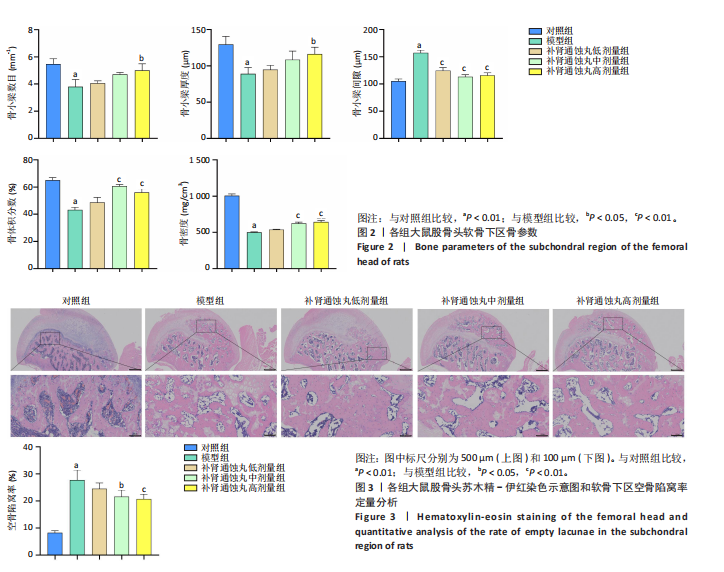

.1 实验动物数量分析 参加实验SD大鼠数量为50只,均进入结果分析。 2.2 Micro-CT检测结果 通过Micro-CT观察各组大鼠股骨头区域骨质变化,见图1。乙醇会导致大鼠股骨头软骨下骨骨量明显减少,骨小梁排列出现紊乱、稀疏等状况,而补肾通蚀丸能够改善上述情况,且呈现一定的剂量效应。模型组骨小梁厚度、骨小梁数目、骨体积分数、骨密度较对照组显著降低(P < 0.01),模型组骨小梁间隙较对照组则显著升高(P < 0.01)。经过不同剂量补肾通蚀丸干预后,各项指标均出现不同程度的逆向改变;其中,与模型组比较,补肾通蚀丸高剂量组骨小梁厚度、骨小梁数目、骨体积分数、骨密度均显著升高(P < 0.05),骨小梁间隙则显著降低(P < 0.05);与模型组比较,补肾通蚀丸中剂量组骨体积分数、骨密度显著升高(P < 0.05),骨小梁间隙则显著降低(P < 0.05);而补肾通蚀丸低剂量组仅在骨小梁间隙指标上较模型组显著降低(P < 0.05),见图2。 2.3 苏木精-伊红染色结果 与对照组比较,模型组大鼠股骨头出现核固缩现象,多见脂肪空泡,部分骨小梁出现断裂、变细;补肾通蚀丸低、中、高剂量组骨细胞核固缩和脂肪空泡较模型组有所减少;在整体结构方面,补肾通蚀丸低剂量组骨小梁变细现象较模型组未见明显改善,但断裂情况有所改善;而补肾通蚀丸中、高剂量组骨小梁断裂、变细情况较模型组均明显改善,见图3;在空骨陷窝率方面,模型组较对照组显著增高(P < 0.01);补肾通蚀丸中、高剂量组较模型组有所降低(P < 0.05),见图3。 2.4 免疫组化染色结果 与对照组比较,模型组NLRP3、Caspase-1、消皮素D蛋白表达明显增强,而Runt相关转录因子2、骨钙素、Ⅰ型胶原蛋白表达显著降低(P < 0.01);与模型组比较,补肾通蚀丸中、高剂量组能够显著降低NLRP3、Caspase-1、消皮素D蛋白表达,且促进Runt相关转录因子2、骨钙素、Ⅰ型胶原蛋白表达(P < 0.05),而补肾通蚀丸低剂量组骨钙素、Ⅰ型胶原蛋白表达有所上调(P < 0.05),其余指标则无明显差异(P > 0.05),见图4,5。 2.5 ELISA检测结果 与对照组比较,模型组大鼠血清中白细胞介素18和白细胞介素1β水平显著增高(P < 0.01);与模型组比较,补肾通蚀丸各剂量组大鼠血清中白细胞介素18和白细胞介素1β水平均显著降低(P < 0.01),且以一定剂量依赖方式递减,见图6。 2.6 Western blot检测结果 与对照组比较,模型组大鼠股骨头组织中NLRP3、cleaved-Caspase-1、Caspase-1、消皮素D、消皮"